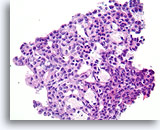

Ductaal carcinoom, Borst FNA, Celblok.

Kleine vergroting van de patiënt in afbeelding 65-66 toont de discohesieve monotone ductale celpopulatie met gerandomiseerde polariteit en een solide groeipatroon.

10X

Ductaal carcinoom, Borst FNA, Celblok.

Kleine vergroting van de patiënt in afbeelding 65-66 toont de discohesieve monotone ductale celpopulatie met gerandomiseerde polariteit en een solide groeipatroon.

10X

Ductaal carcinoom, Borst FNA, Celblok.

Er is duidelijk gerandomiseerde polariteit van een cytologisch atypische en vrijelijk stratificerende populatie ductale cellen aanwezig.

60X

Ductaal carcinoom, Borst FNA, Celblok.

Er is duidelijk gerandomiseerde polariteit van een cytologisch atypische en vrijelijk stratificerende populatie ductale cellen aanwezig.

60X